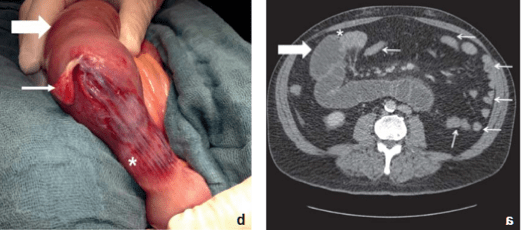

Die Diagnostik stützt sich auf die klinische Untersuchung (geblähtes Abdomen, Darmgeräusche, etc), Anamnese (Obstipation, Übelkeit, Erbrechen, etc) und als Goldstandard das CT (Spiegelbildung, Kalibersprung).

Mechaninscher Ileus (1)